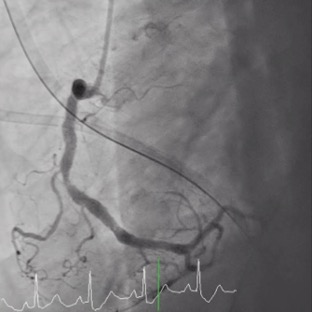

Relevant Catheterization Findings

Coronary angiography(CAG) was done and showed Right Coronary artery(RCA) segment 2 70% stenosis, 75% stenosis at distal Left Main coronary artery(LM) and 90% stenosis at middle Left Anterior Descending artery (LAD), along with a 90% stenosis at the Left Circumflex artery (LCX) orifice. Due to the patient could only afford one Drug-Eluting Stent(DES), so our initial strategy: a Bare-Metal Stent(BMS) at the middle part of LAD and one DES stent crossing over LM-LAD with final kissing.